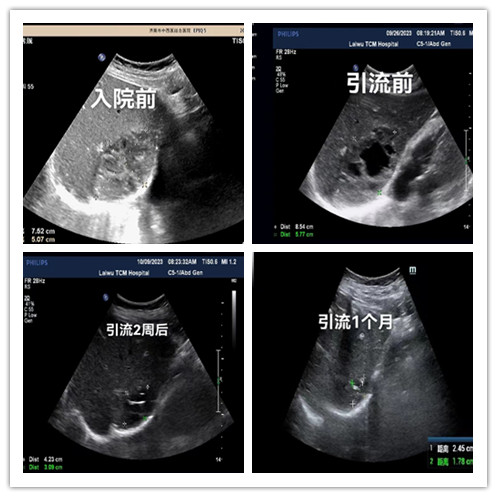

我院超聲科成功完成首例超聲引導下(xià)肝膿腫穿刺置管引流術